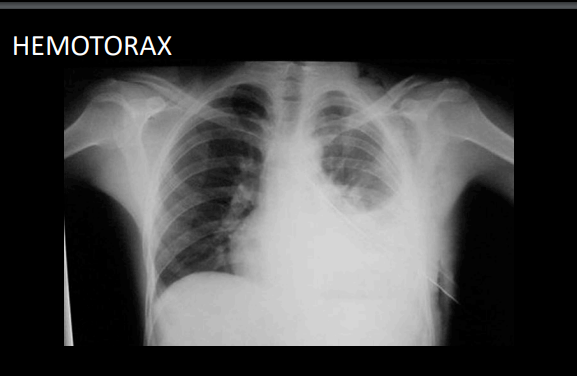

Acumulación de sangre en espacio pleural

signos que se observan en rx de px con hemotorax

derrame pleural

borramiento de silueta cardiaca